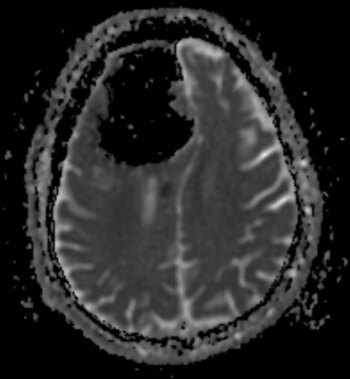

La sorpresa llevó luego de realizarle una tomografía y una resonancia magnética. No podían creerlo: prácticamente todo el lóbulo frontal derecho de este sujeto estaba desaparecido. Solo veían un espacio en blanco (o en negro).

Según determinaron, el paciente sufría de neumocefalia, la presencia de aire en el cráneo, una condición que suele presentarse en casos de cirugía al cerebro, infecciones o heridas faciales, aunque con burbujas o espacios de aire mucho más pequeños.

En este caso, la cavidad llegaba a medir casi nueve centímetros de largo en su parte más grande, algo difícil de encontrar en los libros de historia médica.

La causa más probable, según el equipo de investigadores, fue un tumor benigno formado en los senos paranasales del paciente, que erosionaron la base del cráneo y permitieron la formación de la cavidad.